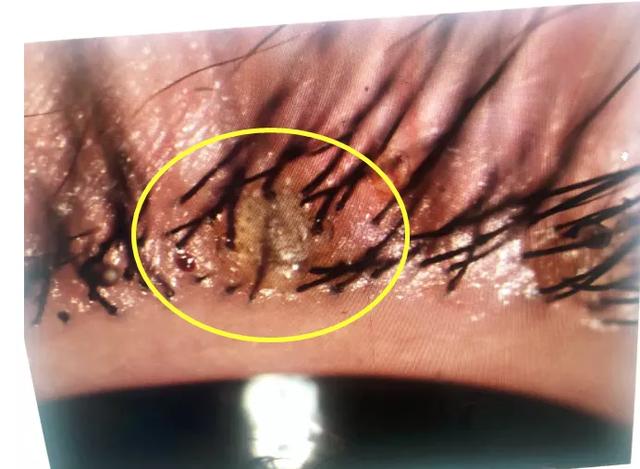

主治医生在检查中发现

她睫毛根部竟然挂着几十粒

未孵化的黑色虫卵及孵化后的白色卵壳

仔细观察之下

【生活■活久见!2岁女孩睫毛密密麻麻长出这了这些,医生都惊呆了】还有白色的虫子在蠕动

医生在裂隙灯下夹起吸附在甜甜睑缘上的虫卵 , 剪去睫毛 , 经反复确认阴虱和虫卵全部除尽后 , 再进行局部清洗、上药 。 经查实 , 这些小虫子是阴虱 , 有二十多只 。 取出的睫毛、成虫还有虫卵都要进行统一焚烧 。